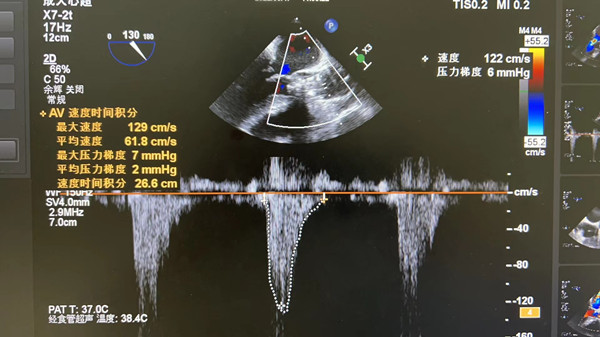

在我院心外科裴斐主任医师,麻醉科刘鹏斌主任医师、罗斌主治医师,超声科韩东刚副主任医师、金鑫主治医师,曹春晖护士长领导的护理团队等多学科协助下,韩振华主任、王新宏副主任医师、刘小军主治医师等先为患者行冠脉造影提示右冠近段95%狭窄(图1),先行PCI干预,右冠植入3.0x22mm支架1枚(图2)。后成功为患者植入TAV24mm VitaFlow瓣膜系统,DSA造影显示主动脉瓣位置良好,未见明显瓣周漏(图3),左右冠脉造影正常,术后即刻心脏超声示最大跨瓣流速129cm/s,最大跨瓣压差7mmHg(图4),顺利结束手术。